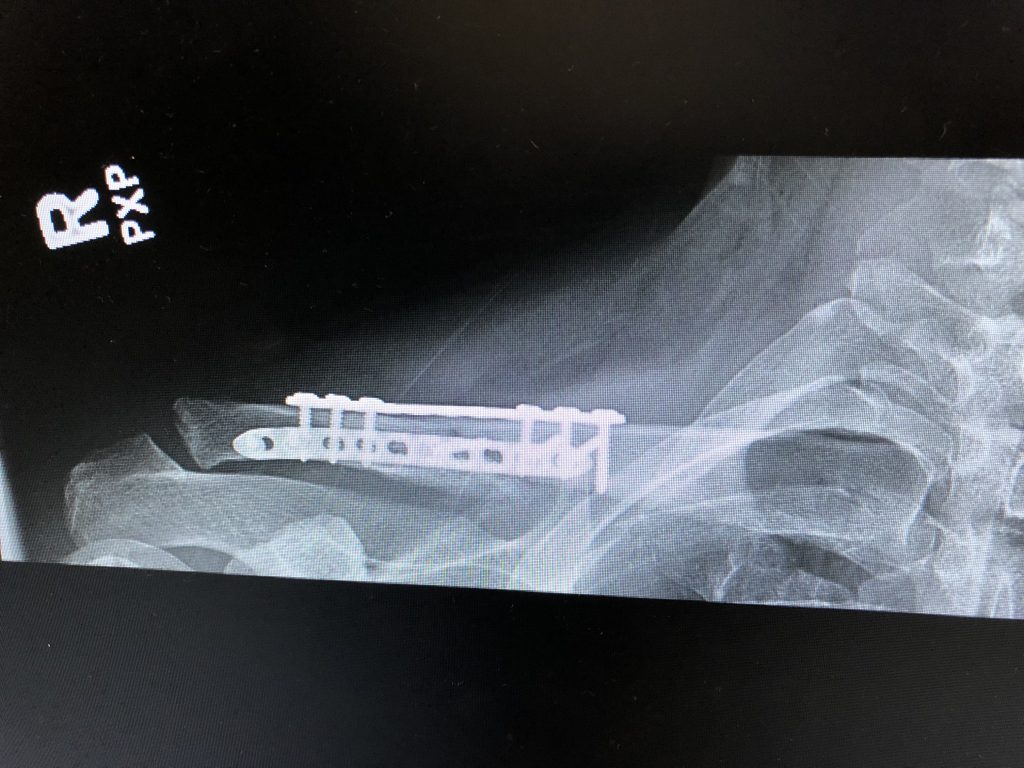

I broke my collarbone in several places after taking a hard fall from my electric longboard. I initially saw another orthopedic surgeon, but his empathy left something to be desired. Upon getting a second opinion with Dr. DiFelice, I knew I had come to the right doctor. His team took exceptional care of me and Dr. DiFelice took the time to explain my options and recommend surgery as the best course of action.

It took two plates and 13 screws to repair my collarbone. After seven weeks in a sling and with his team’s recommendation on a physical therapist; I can wholeheartedly say I’m Back in the Game!